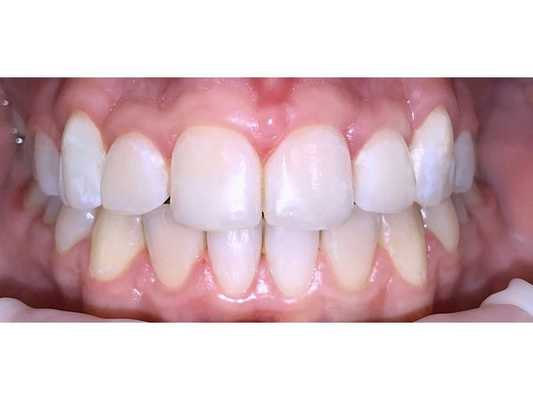

Через 21 месяц контакты между антагонистами восстановились (первый класс Энгля), была устранена скученность, жалобы со стороны височно-нижнечелюстного сустава отсутствовали.

Брекет-систему сняли и зафиксировали несъёмные ретейнеры, также были изготовлены съёмные ретейнеры на обе челюсти. Пациентке рекомендовано носить капы и провести реминерализирующую терапии. Следующий приём назначен через 3 месяца.